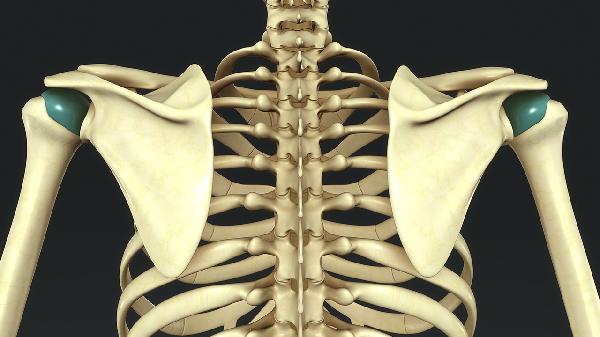

胸椎8压缩性骨折最好的治疗方法

胸椎8压缩性骨折的治疗方法主要有卧床休息、支具固定、药物治疗、微创手术和开放手术。具体选择需根据骨折程度、患者年龄及并发症等因素综合评估。